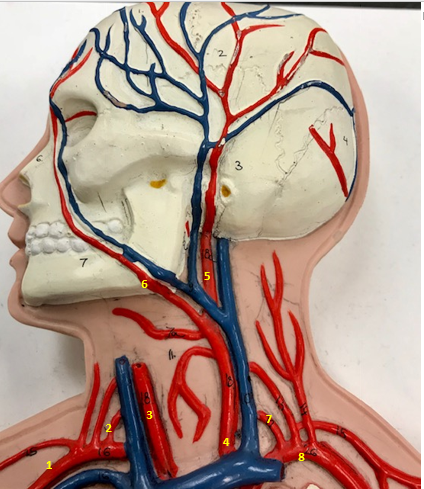

Right subclavian artery

Name #1

Supplies blood to right arm and shoulder

Function of right subclavian artery (1)

Right vertebral artery

Name #2

Supplies blood to brain and spinal cord

Function of right vertebral artery (2)

Right common carotid artery

Name #3

Supplies blood to right neck and head

Function of right common carotid artery (3)

Left common carotid artery

Name #4

Supplies blood to left neck and head

Function of left common carotid artery (4)

Left external carotid artery

Name #5

Supplies blood to face neck and skull

Function left external carotid artery (5)

Left facial artery

Name #6

Supplies blood to face and neck

Function of left facial artery (6)

Left vertebral artery

Name #7

Supplies blood to brain and spinal cord

Function of left vertebral artery (7)

Left subclavian artery

Name #8

Supplies blood to left arm and shoulder

Function of left subclavian artery (8)